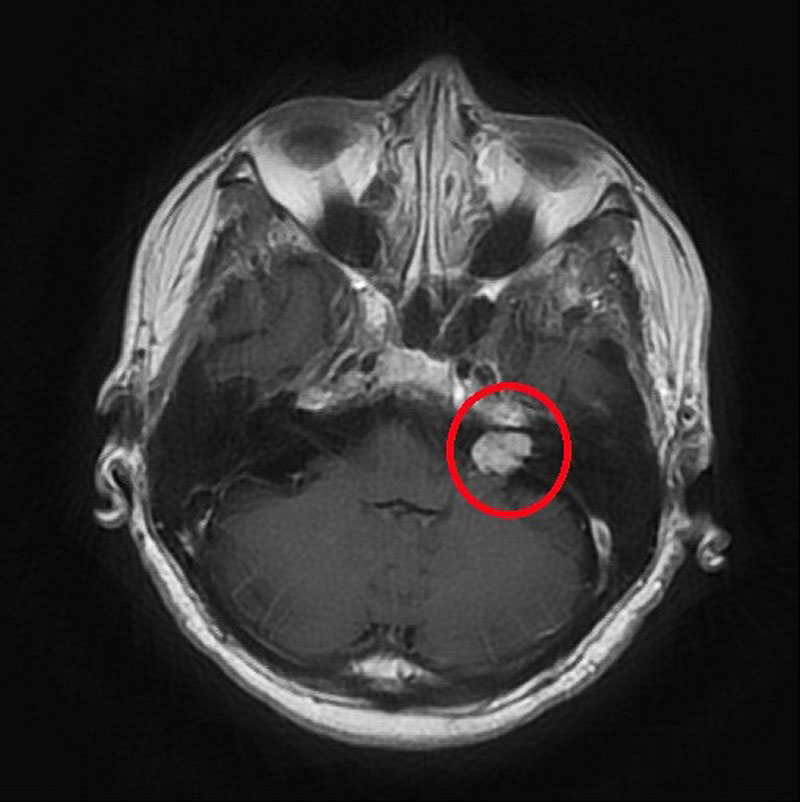

左為手術前的核磁共振掃描,顯示紅圈處有一個小於兩公分大的腫瘤;右為術後電腦斷層,確認腫瘤已完整取出。圖/台北慈院提供